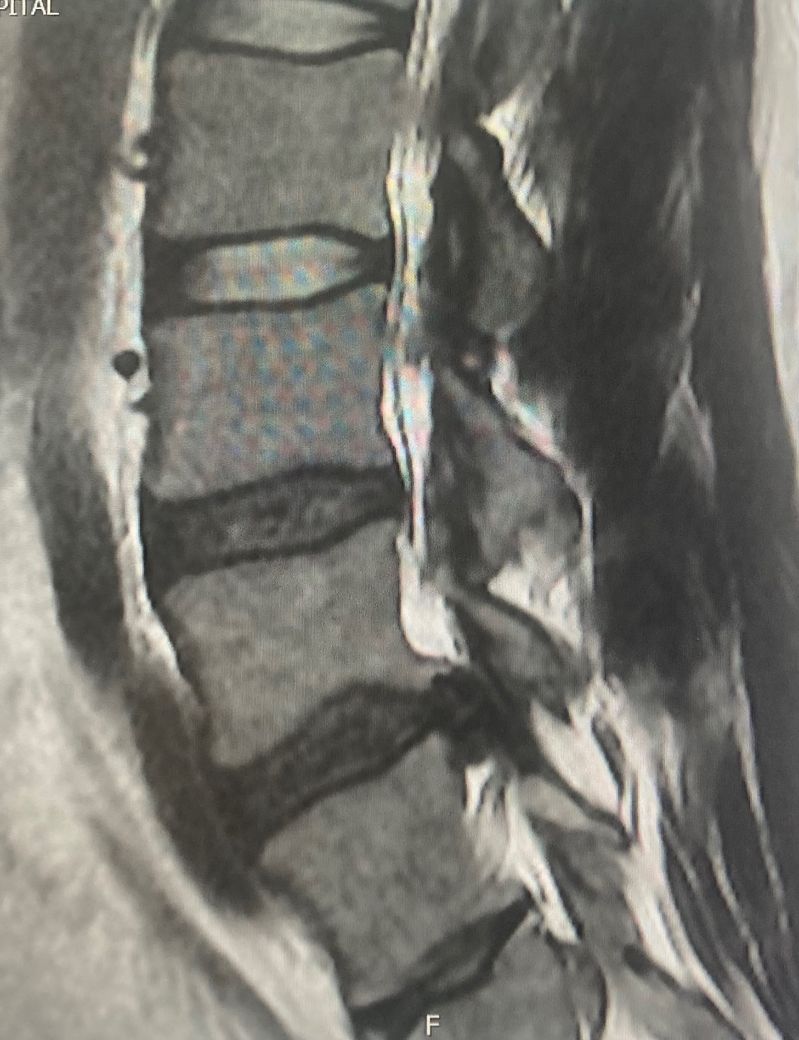

허리디스크 심한 상태인가요? (mri 첨부)

심한 상태 일까요?

수술외엔 치유 방법이 없을까요?

현재 느끼는 통증은

앉기, 걷기, 허리 숙일 때 신경 눌리는 통증이 오고

허벅지 뒷 부분이 저릿저릿한 방사통이 옵니다

통증이 심해서 거동이 안되는 정도는 아니고

불편한 정도입니다

사진으로 볼때 신경을 누르고 있는 것이 확인됩니다.

환자분께서 통증을 느낄만한 상황이네요.

질문하신 "심하다"의 기준은 사진이 아니라 증상으로 판단하는게 맞습니다.

본인이 느끼는 증상의 정도에 따라 답변이 결정될 것 같습니다.

말씀하신 증상 관련 답변 드리자면 현재 움직임에 문제는 없더라도 지속적인 신경 자극이 있다면 증상이 악화될 가능성은 있습니다. 수술이 꼭 필요한 상태인지 여부는 병의 진행 상태와 MRI 등의 추가 검사 포함해서 정형외과 진료를 받아야 정확히 판단할 수 있구요

초기 또는 중등도 증상이라면 물리치료, 약물치료, 신경주사(블록), 운동치료 등의 비수술적 치료로 호전될 가능성도 있습니다.

즉, 정확한 치료 계획은 담당 정형외과 의사와 상의해보셔야 합니다